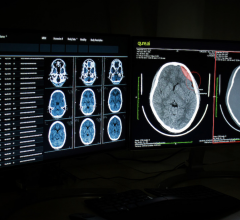

November 4, 2020 — A powerful type of artificial intelligence known as deep learning can help physicians detect ...

October 21, 2020 — Quantib, a market leader in artificial intelligence solutions for radiology, today announced that it ...

October 9, 2020 — A team of researchers at the University of Minnesota recently developed and validated an artificial ...